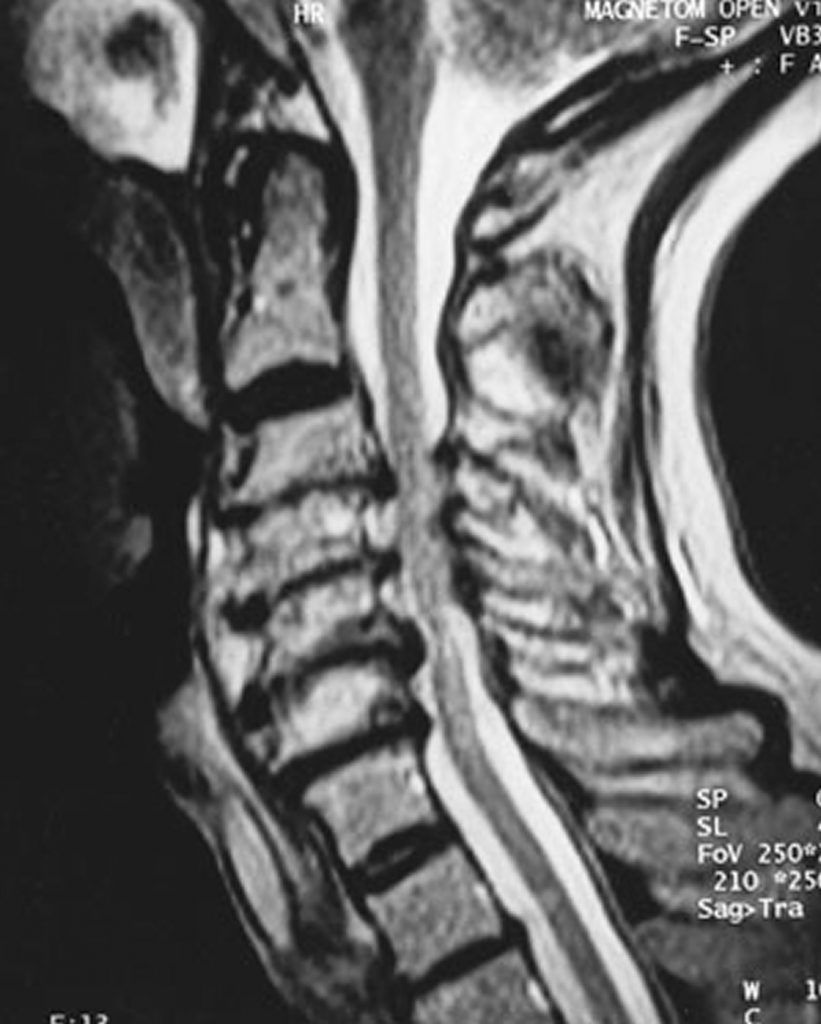

MRI Cervicalspine Shows C4C5 Moderate spinal cord compression Spinal Cord Compression Wikem Suspect in patient with known cancer (esp lung, breast, prostate) + back pain. Our website will remain the same, but for mobile app users, this transition will offer an improved user. See ebq:high dose steroids in cord injury for further discussion; This article will focus on atraumatic causes of spinal cord compression, including degenerative spondylosis with myelopathy,. Various lesions can. Spinal Cord Compression Wikem.

Spinal cord compression MRI wikidoc Spinal Cord Compression Wikem Spinal cord compression (scc) is a surgical emergency, usually requiring prompt surgical decompression to prevent permanent. Occurs in thoracic location in 70% of patients. Our website will remain the same, but for mobile app users, this transition will offer an improved user. Suspect in patient with known cancer (esp lung, breast, prostate) + back pain. In patients >10yr, majority of. Spinal Cord Compression Wikem.